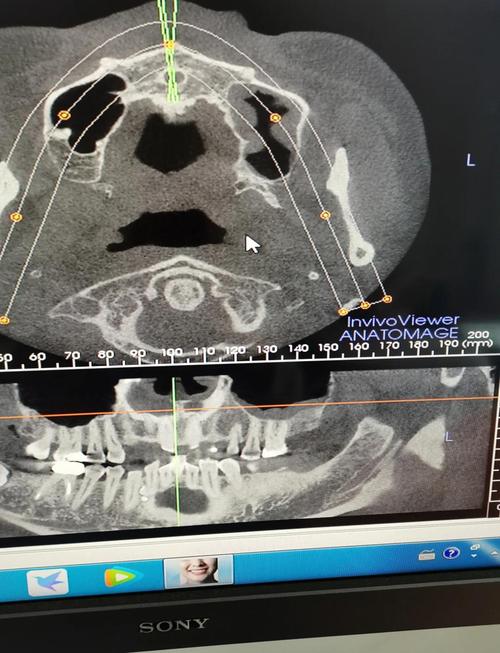

(图片来源网络,侵删)

(图片来源网络,侵删)- 一线城市(如北京、上海、广州、深圳):人力和运营成本高,价格通常比二三线城市贵20%-30%。